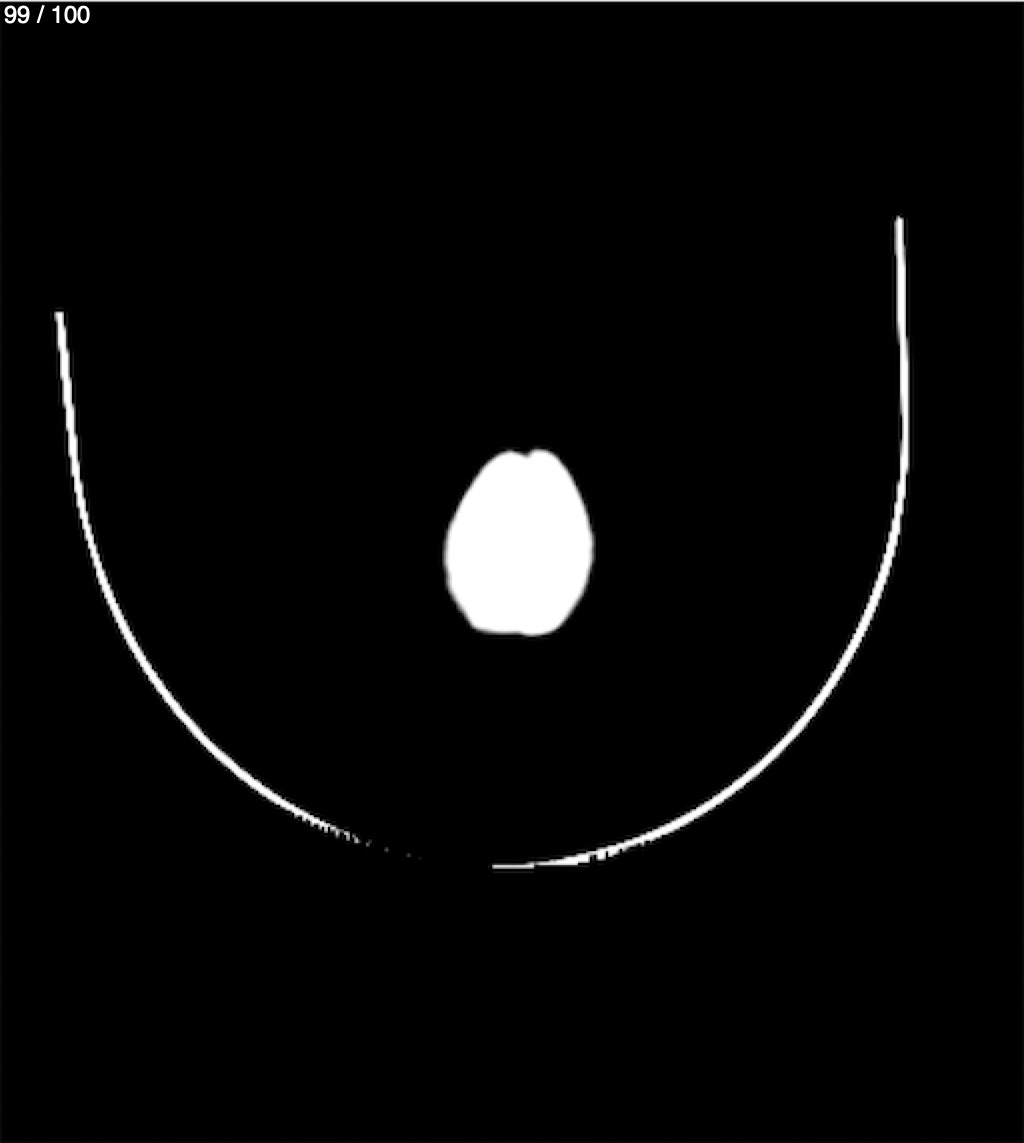

Catarino Perez Escobar 85A - T.C Craneo